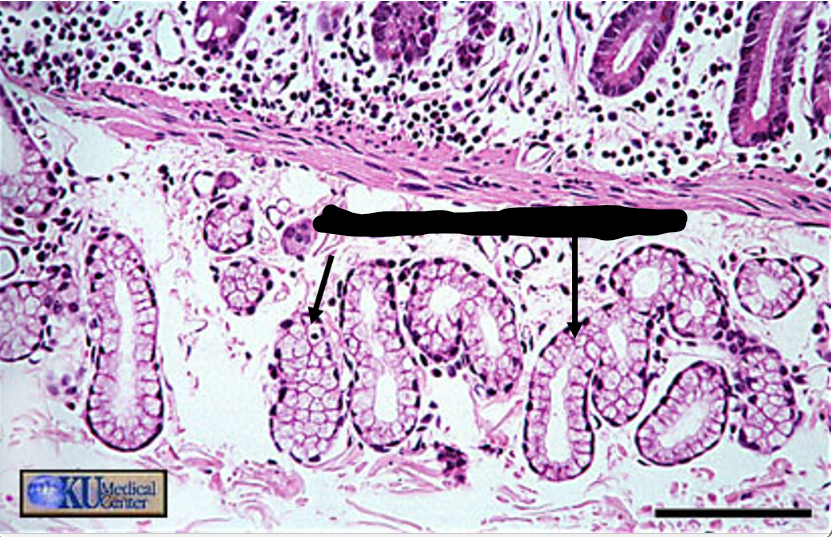

plicae circulares

green

villi

crypts

blue

lamina propria

black

simple columnar epithelium

the arrows point to

brush border/microvilli